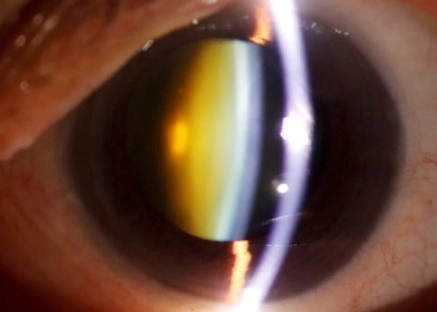

백내장이 발생하면 눈의 수정체가 점차 노랗게 변하며, 이로 인해 색상이 누렇게 보일 수 있습니다. 특히, 파란색과 같은 색상이 덜 선명하게 보일 수 있습니다.